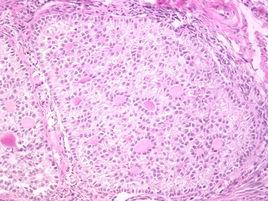

(一)病理組織學檢查:

卵巢性索間質瘤患者中常用的診斷方法,雖然能幫助患者早期確診,但是診斷所需時間相對較長,且診斷具有創傷性,難以重複診斷,導致患者診斷依從性較差。